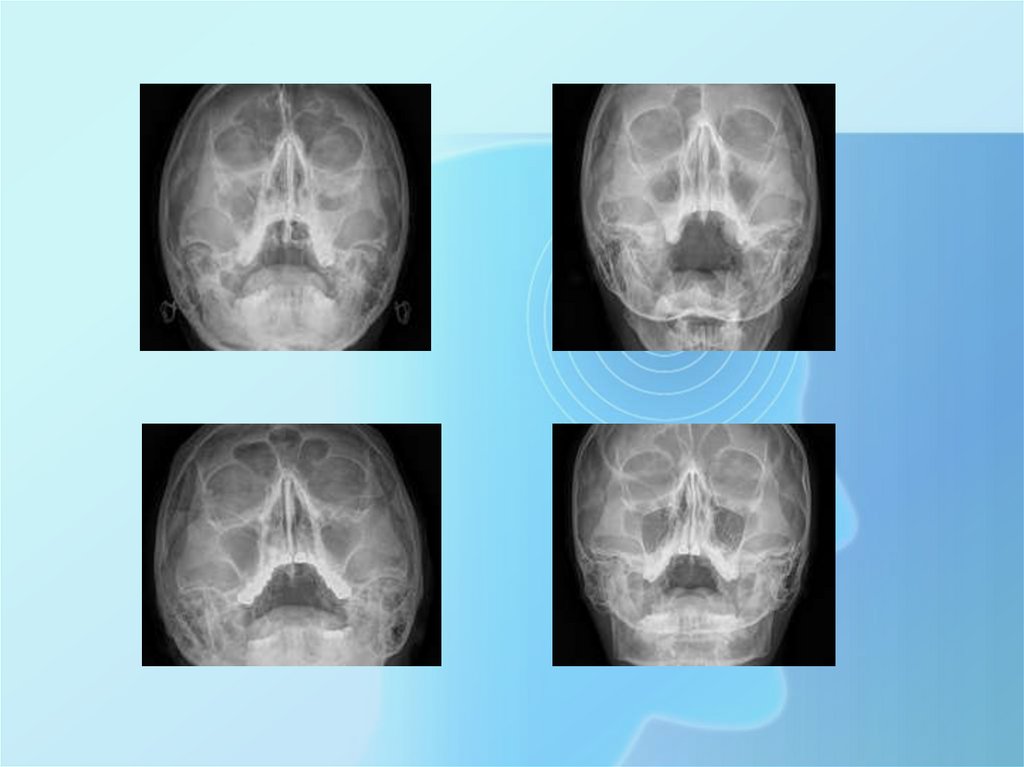

Рентген придаточных пазух носа – это информативное и доступное

диагностическое исследование, которое применяется в диагностике

травм лицевого скелета и заболеваний придаточных пазух, которые

представляют собой изолированные анатомические образования

(полости), заполненные воздухом. В 80% случаев заболеваний – это

острые и хронические синуситы, то есть воспалительные изменения

в придаточных пазухах (гайморит, фронтит и др.). В иных случаях

могут встречаться опухоли, остеомы, инородные тела.

На рентгеновском снимке видны верхнечелюстные (гайморовы)

и лобные (фронтальные) пазухи, основная пазуха, решетчатый

лабиринт, стенки глазниц, кости лицевого скелета. На снимке врач

оценивает состояние костной ткани, пневматизацию (воздушность)

носовых пазух, состояние носовой полости и носоглоточного

пространства.

При воспалительной реакции со стороны внутренней оболочки

придаточной пазухи на рентгеновском снимке будут видны

признаки отека слизистой, горизонтальные уровни,

свидетельствующие о скоплении гноя или жидкости в полости

пазух. При этом могут быть поражены как все придаточные пазухи

(пансинусит), так и отдельные их виды: лобные (фронтит),

верхнечелюстные (гайморит).

Исследование не требует предварительной подготовки и

выполняется в затылочно-подбородочной и затылочно-лобной

проекциях в вертикальном положении пациента.

Рентгенография придаточных пазух проводится не только с целью

первичной диагностики и выбора тактики лечения, но и для

контроля качества и эффективности проводимой терапии. В

спорных вопросах интерпретации рентгенологического

изображения пазух прибегают к более точным методам

исследования – компьютерной томографии.